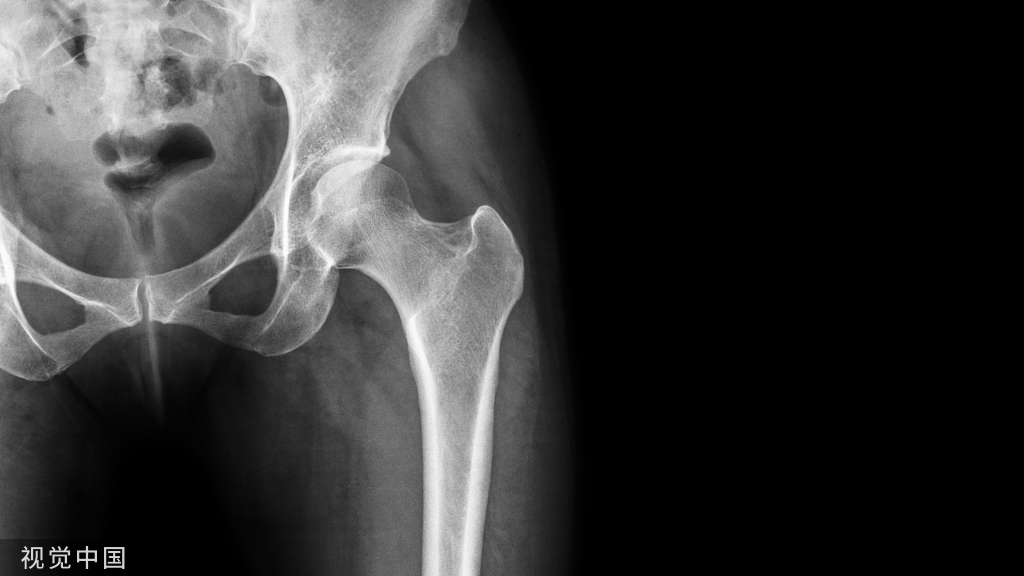

(五)、股骨动力髋、动力髁、空心钉、三针、钢板手术的体位

- 患者平卧位,头下置头圈,健侧上肢用束臂带固定于搁手架上,患侧上肢加软垫保护置于胸前或头部。

- 髋部垫一小方垫,约抬高患处15°~30°充分暴露术野。

- 健侧下肢膝下及足下垫一方垫,膝部放一海绵垫约束带固定。